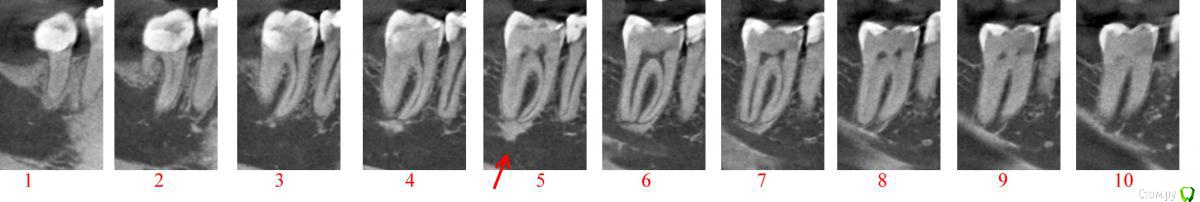

2. Судя по КТ в зубе 2 корня, 3 канала. Два канала в одном из корней связаны "перемычкой" на всём протяжении. Возможно, инфекция в "перемычке"?  Нужно ли "проходить" эту перемычку, объединять два канала в один? Впрочем, это уже мои домыслы, доктор наверняка знает, и всё же ваше мнение. На КТ очень хорошо видно.

3. Под корнями кость чуть-чуть уплотнена (см стрелку) - что это?

Привожу срезы КТ зуба до депульпирования. В 2х проекциях.